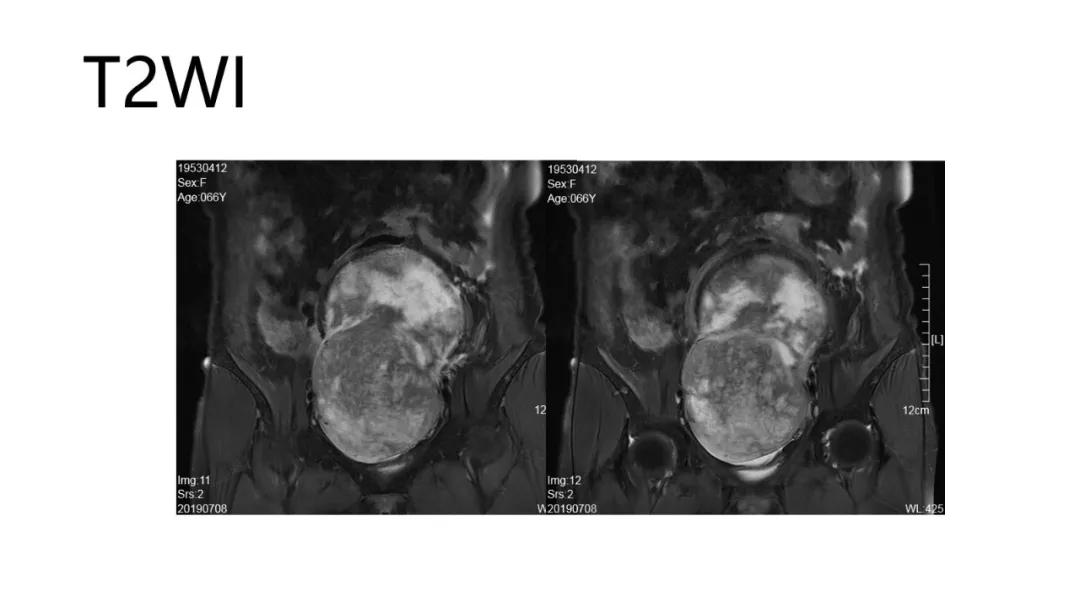

病理:颗粒细胞瘤

病理:子宫肌瘤粘液样变性